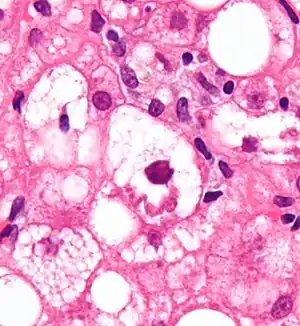

Micrograph showing a Mallory body with the characteristic twisted-rope appearance (centre of image - within a ballooning hepatocyte). H&E stain.

Mallory bodies are highly eosinophilic and thus appear pink on H&E stain. The bodies themselves are made up of intermediate cytokeratin 8/18 filament proteins that have been ubiquitinated, or bound by other proteins such as heat shock proteins, or p62/Sequestosome 1.[5]